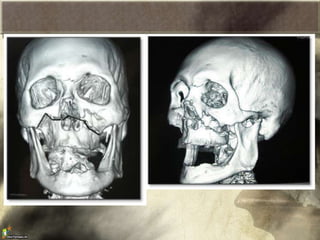

Fracturas faciales:

• Importancia estética y funcional

• Rara vez ponen en peligro la vida

• Mayor éxito cuando se tratan de manera temprana

(1° semana)

• Principal causa: traumatismos

• Valorar lesiones asociadas

Lesiones que afectan huesos y tejidos blandos

de tres áreas anatómicas.

Tercio superior.

Tercio medio.

Tercio inferior.

• El 80% se produce por accidente de transito

Fracturas de Maxilar inferior

• Al fracturarse la mandibula se producen 3

zonas distintas:

– Tension

– Neutra

– Presion

• La accion de los musculos masticadores

pueden “ayudarnos” a que no se desplaze la

fractura, o puede perjudicarnos dependiendo

del trazo

Fracturas de maxilar superior

• Clasificacion LeFort

– Tipo I: fractura entre borde infraorbitario y la

raiz de los dientes (es horizontal)

– Tipo II: fractura en forma piramidal por

debajo del reborde de la orbita y la region

nasofrontal

– Tipo III: fractura que abarca el arco

cigomatico, pared lateral de la orbita y la region

nasofrontal (mas grave)

• Rara vez se ven de forma pura.